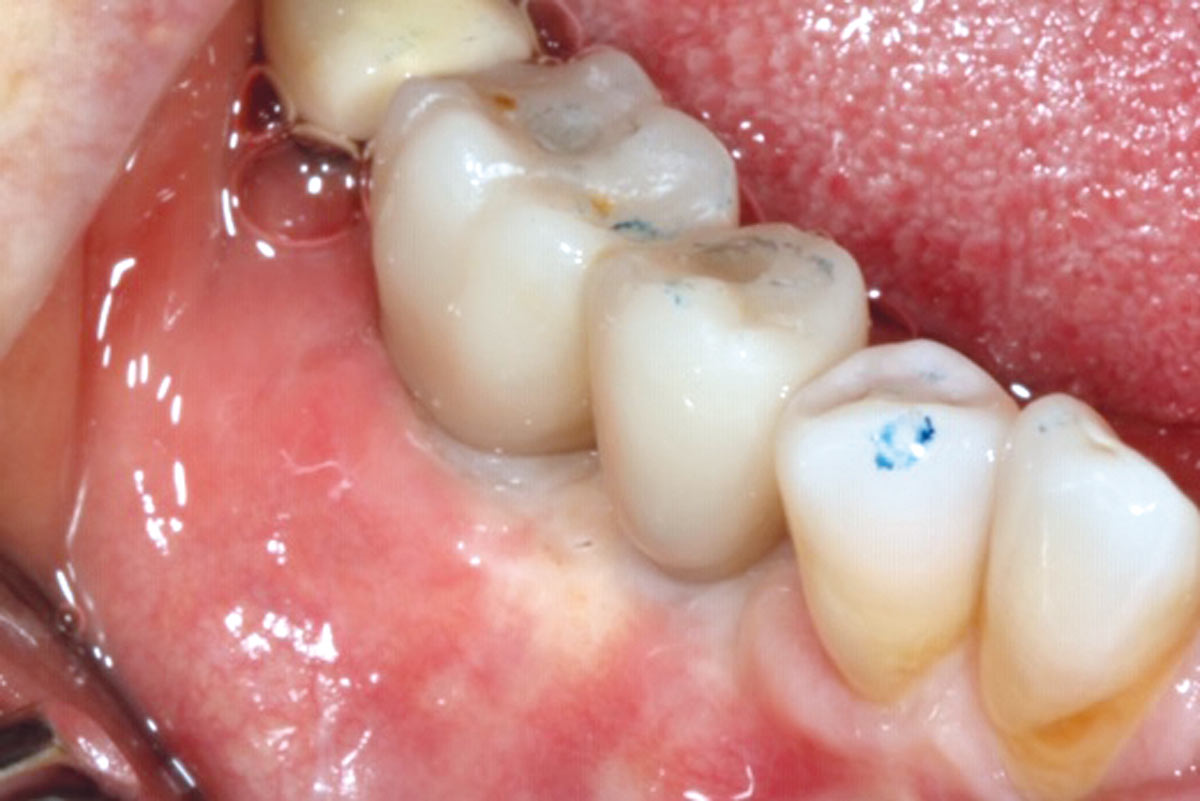

2/10 - Bone defect.GBR with cerabone® and Jason® membrane DentalPro - Dr. A. Gargiulo